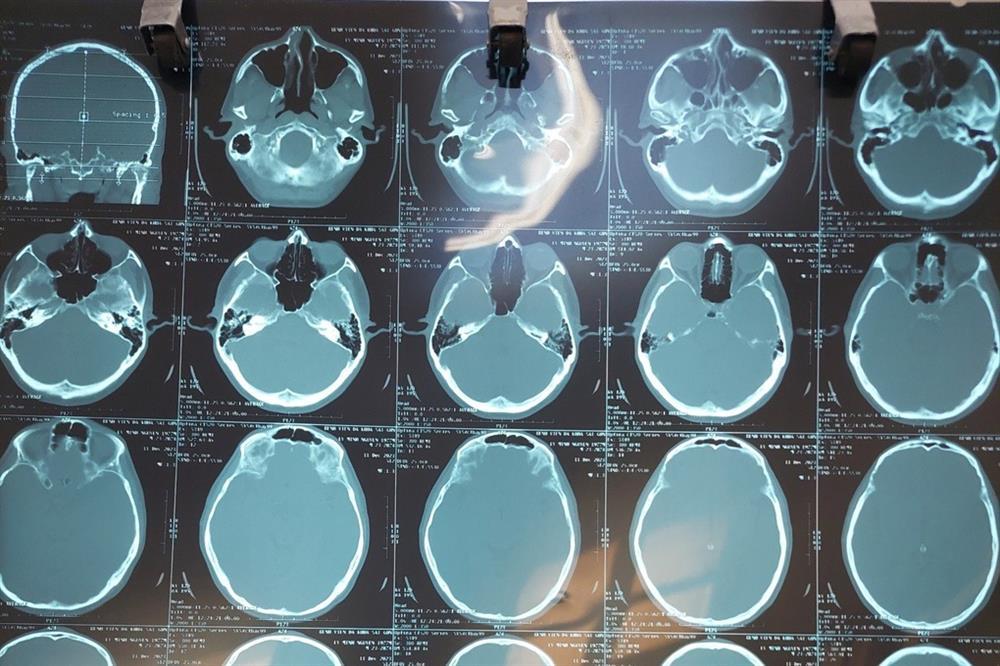

Ảnh chụp chiếu của bệnh nhân bị gãy xương chính mũi (Ảnh: TH).

Trường hợp thứ hai là anh N.M.C. (SN 1964) nhập viện với chẩn đoán chấn thương đầu, có vết thương tại trán. Nặng nhất là trường hợp của bệnh nhân L.M.N. (SN 1977) khi bị chấn thương đầu, gãy xương chính mũi.